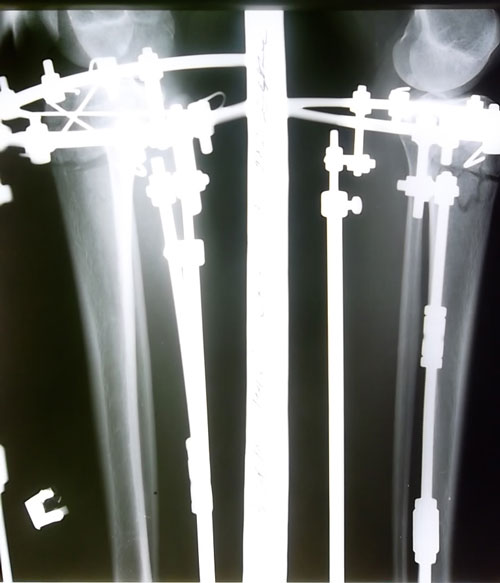

Сегодня 19 день после ОП. Крутки закончились, вчера мы делали рентгеновские снимки. Судя по снимкам кости ровные, левая ножка даже немного иксит, хотя по фото не скажешь. Как будто она все еще кривая.